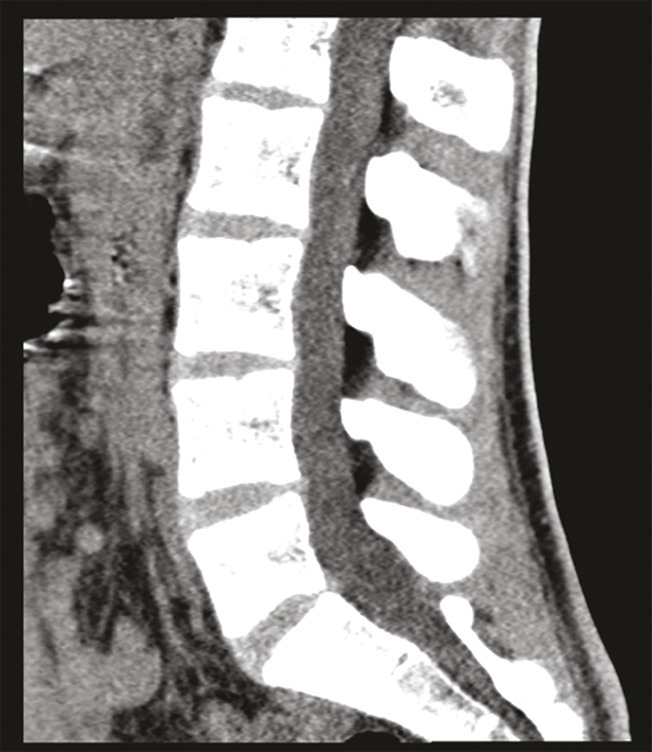

Le bilan sanguin et l’analyse urinaire sont normaux. Les sérologies de la syphilis et du virus de l’immunodéficience humaine (VIH) ainsi que les PCR (polymerase chain reaction) pour Chlamydiæ et Neisseria gonorrhoeæ sont négatives. Une tomodensitométrie lombosacrée, réalisée en urgence, exclut un conflit discoradiculaire et une compression médullaire (fig. 1).

Une imagerie tomodensitométrique du pelvis et de la colonne lombaire permet d’exclure un conflit radiculaire, une hernie discale ou une compression médullaire.